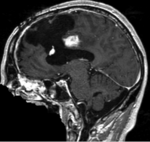

BSpline (7x7x7) unmasked

BSpline (7x7x7) masked

nonrigid registered (7x7x7 BSpline unmasked) nonrigid registered (7x7x7 BSpline masked)